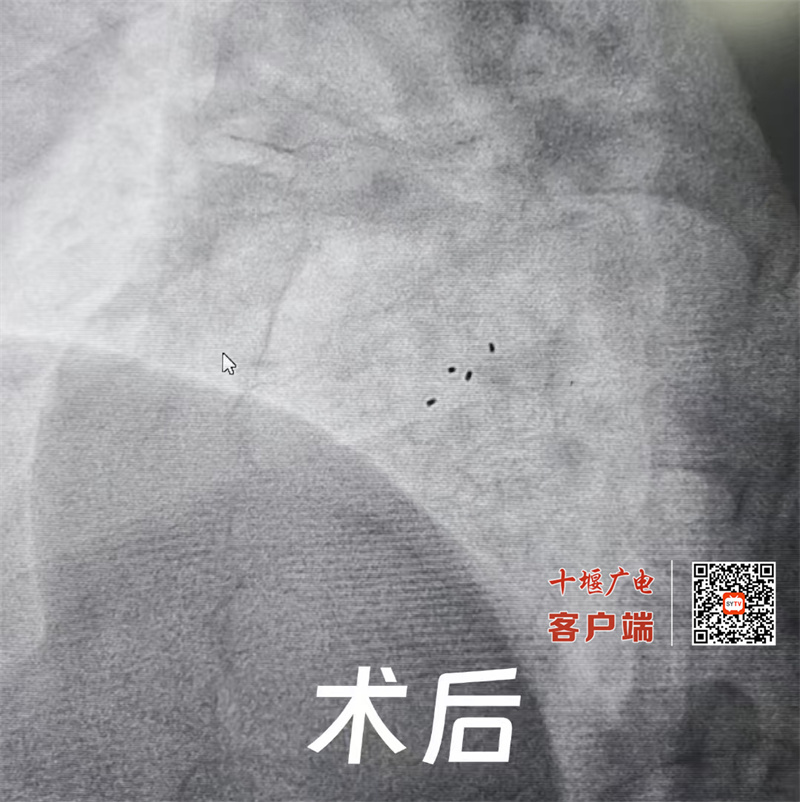

据了解,患者为一名中年女性,头痛病史多年,明确诊断为卵圆孔未闭。后找到十堰市人民医院心血管内科一病区主任赵继先。经综合评估其符合介入手术指征。由于目前临床中常规的卵圆孔未闭封堵器都是合金材质,而患者既往还有金属过敏史,只能通过生物可降解封堵器实施卵圆孔未闭(PFO)封堵术。但可降解封堵器植入对手术团队要求很高,一般医院不能独立完成。赵继先主任、副主任医师范群雄经过充分的讨论和准备,决定联合医院麻醉科、超声影像科,一起为该女士实施可降解卵圆孔未闭封堵器植入术。手术当天,通过超声探头实时监测患者的心脏结构和血流情况,封堵器精准安全到达心脏卵圆孔未闭处,可降解封堵器展开、锁定、释放,一气呵成,即刻超声下观察,封堵器像两把保护伞,牢牢贴合房间隔,封堵住卵圆孔,无残余分流,手术圆满成功!

十堰市人民医院心血管内科一病区范群雄副主任医师介绍,卵圆孔未闭(PFO)是一种常见的先天性心脏结构异常,有大量右向左分流的PFO,可能会导致偏头痛、脑卒中等并发症。传统的卵圆孔未闭封堵器通常是由金属材料制成,需要永久留在患者体内,而可降解卵圆孔未闭封堵器则是由生物可降解材料制成,植入人体内起到临时封堵作用,自体组织修复后,材料自然降解为无害的二氧化碳和水,没有任何异物残留,能够恢复心脏的正常结构和功能。